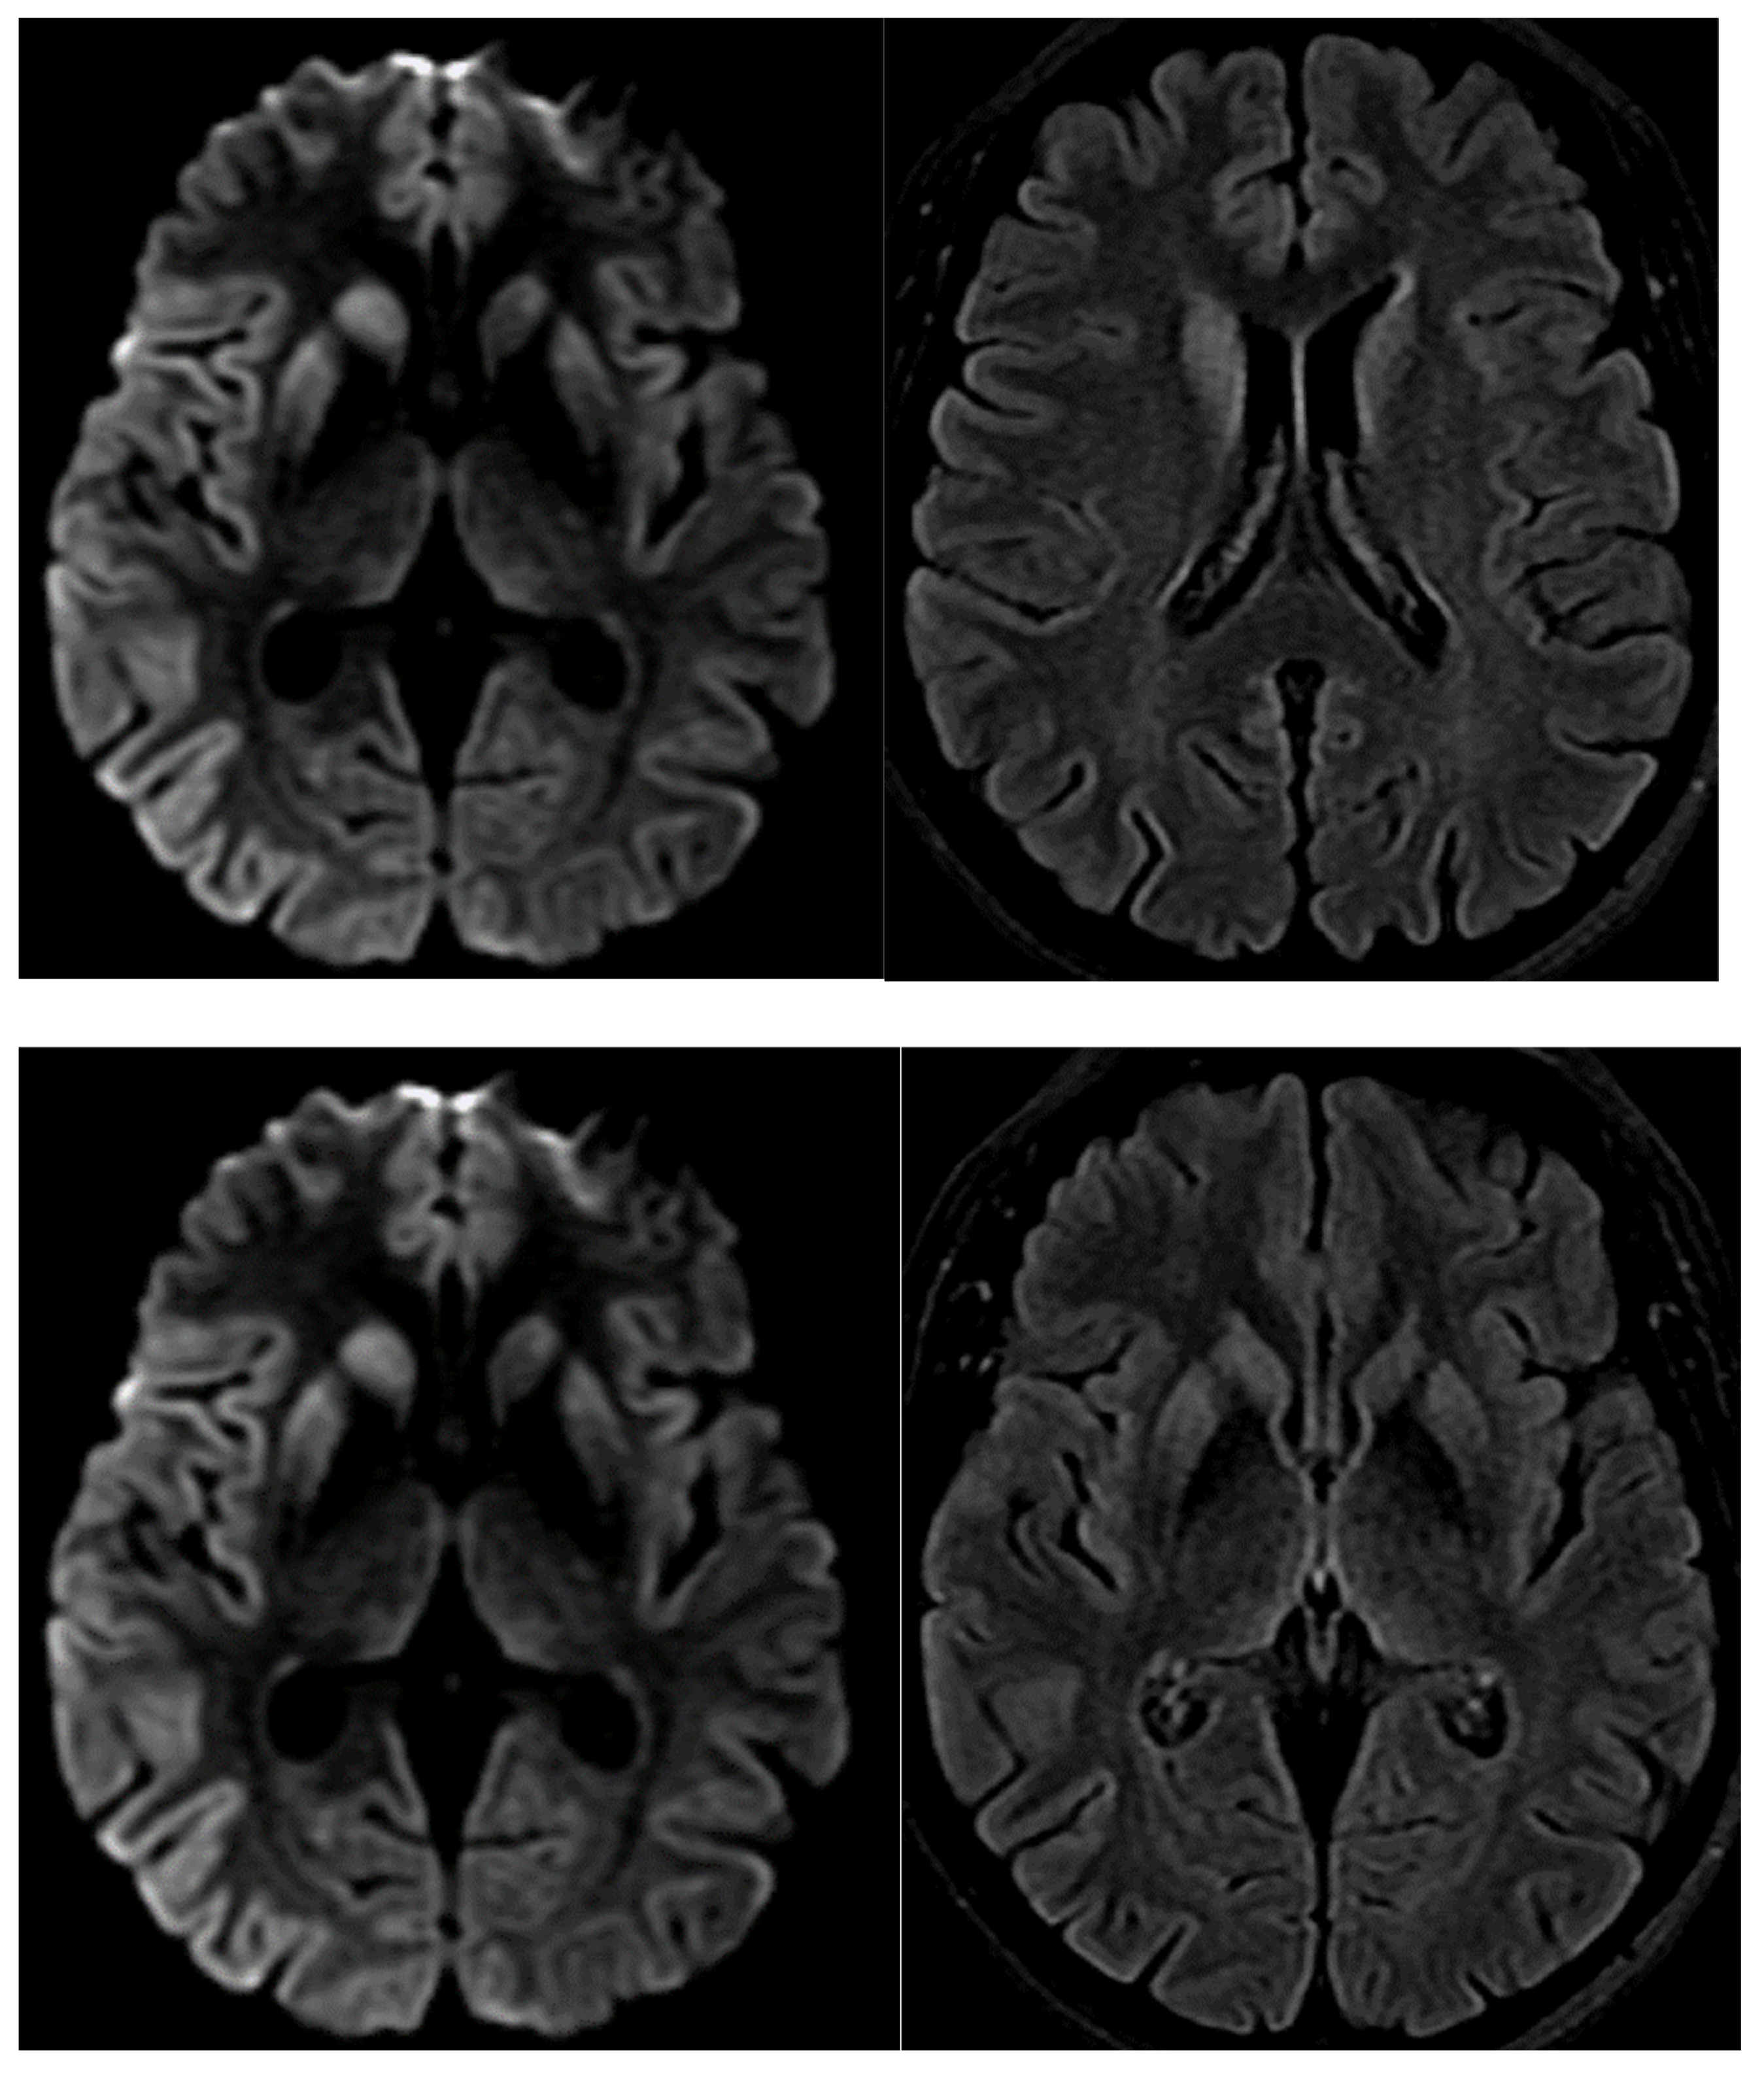

Magnetic resonance imaging (MRI) of the brain revealed restricted diffusion with the corresponding fluid-attenuated inversion recovery (FLAIR) in the caudate nucleus and putamen, bilaterally, and cortical ribboning in the right occipito-parietal cortex (Figure 3).

Figure 3.

DWI, diffusion-weighted imaging abnormalities, typically reported in CJD in the cortical and basal ganglia.

About 15% of human prion diseases or transmissible spongiform encephalopathies (TSE) are associated with PRNP mutation: E200K is highly prevalent in European countries [10], including in Italy, and beyond, in Chile, and in Jewish families of Libya and Tunisia [11]. Interestingly, despite the classical symptoms (confusion, dementia, mutism, and an akinetic state), an unpredictable spectrum of onset and clinical presentation have been documented not only within the subtypes, but also within the same CJD family, even between monozygotic twins. In particular, the mutation at codon 129 can be linked to different clinical phenotypes depending on whether the mutation co-segregates with methionine (FFI) or valine (VAL) [12,13]. A striking example of this phenotypic variability is our family, in which PRNP sequencing was unfortunately performed only in our proband, who rapidly progressed and died two months after disease onset, differently from her parental aunt. She, too, presented the typical MRI findings described in a cluster of high incidence of CJD occurring among a Libyan Jew family living in Israel [14], caused by an E200K mutation,: with gray matter atrophy, FLAIR, or DWI hyperintensities in the basal ganglia and thalamus. Notably, their death occurred within 1 year of the MR studies, while our proband died earlier in two months.